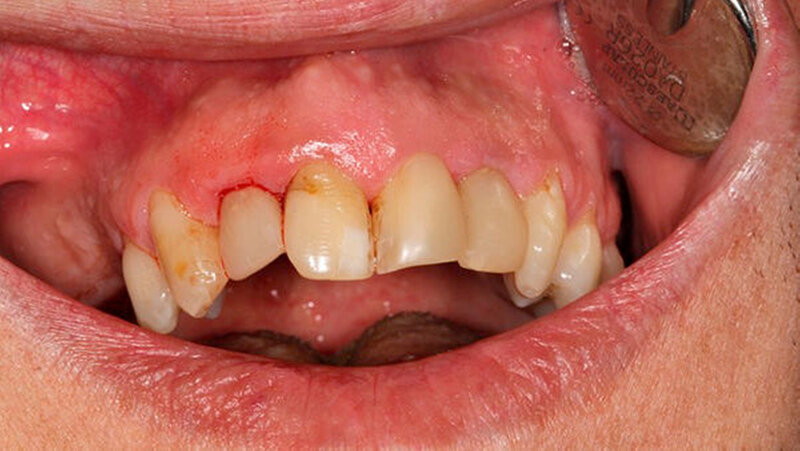

Oralchirurg Marcus Stoetzer arbeitete drei Monate lang im Feldlager der Bundeswehr in Mazar e Sharif - insgesamt behandelte er in Afghanistan 298 Soldaten. Die Bilder zeigen, aus welchem Grund sie zu ihm kamen.